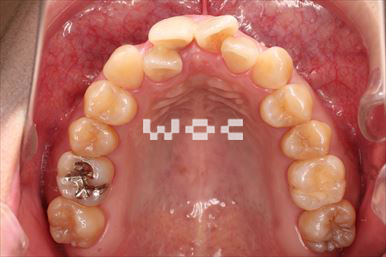

治療前1

治療前2

出っ歯舌側矯正

上下舌側矯正を希望。

通院状況や歯みがきの協力が良かったため、1年7ヶ月で治療を終えることができました。※装置と注意事項に関しては、大人の矯正装置一覧へ。

- 年齢:20歳女性

- 主訴:出っ歯が気になる

- 基本矯正料金:120万円

- 治療期間:1年7ヶ月

- 抜歯部位:上顎両側第一小臼歯